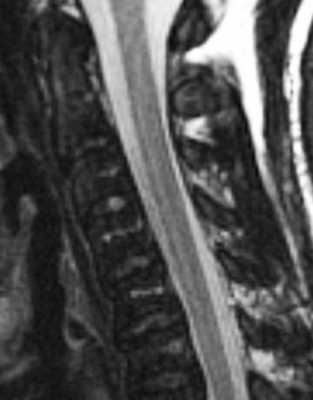

(Слева) Сагиттальный срез, Т2-ВИ, 15-летний пациент: жировая перестройка костного мозга, ограниченная зоной вокруг центральных дренирующих вен каждого позвонка. Остальная часть тел позвонков заполнена красным костным мозгом. Подобная МР-картина типична для пациентов молодого возраста.

(Справа) На сагиттальном Т1-ВИ 50-летнего пациента определяется смешанная картина «ткани в горошек», характеризующаяся перемежающимися друг с другом участками красного и желтого костного мозга. Жировой костный мозг обычно локализуется вокруг дренирующих вен и вблизи замыкательных пластинок. Красный костный мозг характеризуется аналогичной или несколько повышенной по сравнению с мышцами интенсивностью сигнала.

(Слева) На сагиттальном Т1-ВИ 85-летнего пациента определяется практически полная жировая перестройка костного мозга тел позвонков, на фоне которой видны лишь небольшие фокусы эритропоэтического костного мозга. Красный мозг с возрастом подвергается инволюции, однако небольшие его очаги в позвонках, если пациент ранее не получал лучевую терапию, сохраняются всегда.

(Справа) Сагиттальный срез, Т1-ВИ: выраженная разница в интенсивности сигнала между нормальным желтым костным мозгом, изменениями костного мозга на фоне лучевой терапии и опухолевой инфильтрацией костного мозга.